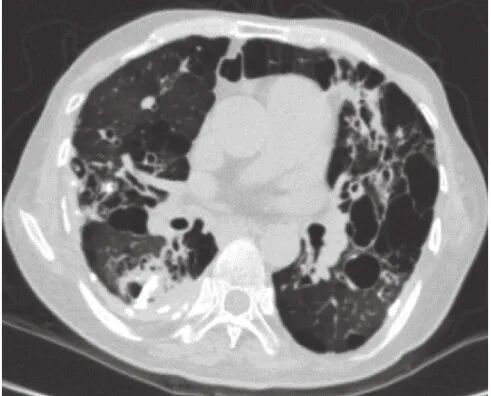

患者6,男,29岁,无吸烟史,11年前反复气胸行肺大疱切除术,术后左上肺可见支扩,7年前出现咳嗽,外周血嗜酸性粒细胞百分比增高,4年前咳嗽加重,咳黄色痰栓,血清IgE 3610 IU/mL,烟曲霉特异性IgE 6.74 kUA/L,外周血嗜酸性粒细胞百分比22.1%,胸部HRCT示左上肺大疱并实变,左舌叶及左下叶可见黏液栓(图4),诊断ABPA,予泼尼松联合伊曲康唑治疗。治疗3个月后IgE降至221 IU/mL,影像表现较前期好转,遂自行停药。后症状反复,再次加用伊曲康唑(200 mg,2次/d)联合泼尼松(30 mg,1次/d)治疗,伊曲康唑口服8个月,泼尼松逐渐减量,2年前(泼尼松治疗12个月后)减至10 mg、1次/d时发现双侧股骨头缺血性坏死,泼尼松逐渐减停。1年前复查外周血嗜酸性粒细胞百分比1.5%,血清IgE 109.6 IU/mL,烟曲霉特异性IgE 0.66 kUA/L。

图4 患者6的HRCT检查像

2018年4月5日,左上肺可见斑片影。